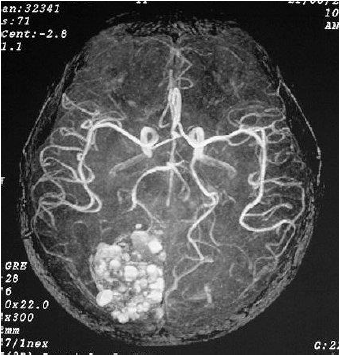

A angiotomografia digital cerebral demonstra a fase

Provas